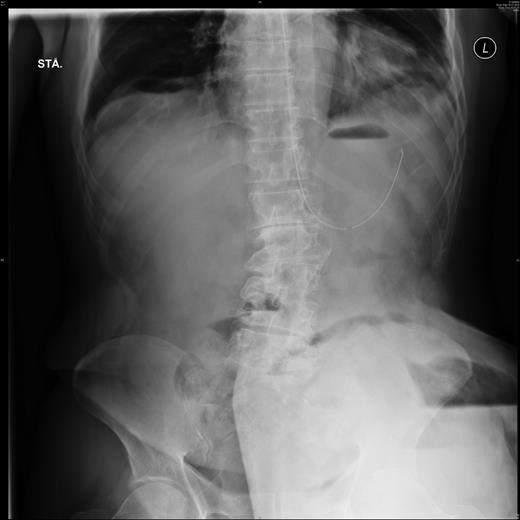

Plain film abdominal x-ray showed not only a large part of the small intestine, but also the stomach located in the PSH with signs of pneumoperitoneum (Fig. 1).

Plain film abdominal X-ray showing the trapped stomach in the large parastomal hernia on the patient's lower left side. Notice the fundus-like air on the outer left-hand side of the trapped part. Also visible is free air inside the parastomal hernia.